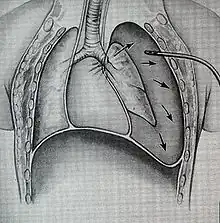

Damage to the airways can cause subcutaneous emphysema (air trapped in the subcutaneous tissue of the skin) in the abdomen, chest, neck, and head.[2] Subcutaneous emphysema, present in up to 85% of people with TBI,[10] is particularly indicative of the injury when it is only in the neck.[13] Air is trapped in the chest cavity outside the lungs (pneumothorax) in about 70% of TBI.[4][10] Especially strong evidence that TBI has occurred is failure of a pneumothorax to resolve even when a chest tube is placed to rid the chest cavity of the air; it shows that air is continually leaking into the chest cavity from the site of the tear.[11] Air can also be trapped in the mediastinum, the center of the chest cavity (pneumomediastinum).[4] If air escapes from a penetrating injury to the neck, a definite diagnosis of TBI can be made.[10] Hamman's sign, a sound of crackling that occurs in time with the heartbeat, may also accompany TBI.[14]

When airways are damaged, air can escape from them and be trapped in the surrounding tissues in the neck (subcutaneous emphysema) and mediastinum (pneumomediastinum); if it builds up to high enough pressures there, it can compress the airways.[2] Massive air leaks from a ruptured airway can also compromise the circulation by preventing blood from returning to the heart from the head and lower body; this causes a potentially deadly reduction in the amount of blood the heart is able to pump out.[7] Blood and other fluids can build up in the airways, and the injury can interfere with the patency of the airway and interfere with its continuity.[2] However, even if the trachea is completely transected, the tissues surrounding it may hold it together enough for adequate air exchange to occur, at least at first.[4]

Treatment of TBI varies based on the location and severity of injury and whether the patient is stable or having trouble breathing,[2] but ensuring that the airway is patent so that the patient can breathe is always of paramount importance.[10] Ensuring an open airway and adequate ventilation may be difficult in people with TBI.[3] Intubation, one method to secure the airway, may be used to bypass a disruption in the airway in order to send air to the lungs.[3] If necessary, a tube can be placed into the uninjured bronchus, and a single lung can be ventilated.[3] If there is a penetrating injury to the neck through which air is escaping, the trachea may be intubated through the wound.[10] Multiple unsuccessful attempts at conventional (direct) laryngoscopy may threaten the airway, so alternative techniques to visualize the airway, such as fiberoptic or video laryngoscopy, may be employed to facilitate tracheal intubation.[10] If the upper trachea is injured, an incision can be made in the trachea (tracheotomy) or the cricothyroid membrane (cricothyrotomy, or cricothyroidotomy) in order to ensure an open airway.[6] However, cricothyrotomy may not be useful if the trachea is lacerated below the site of the artificial airway.[10] Tracheotomy is used sparingly because it can cause complications such as infections and narrowing of the trachea and larynx.[26] When it is impossible to establish a sufficient airway, or when complicated surgery must be performed, cardiopulmonary bypass may be used—blood is pumped out of the body, oxygenated by a machine, and pumped back in.[26] If a pneumothorax occurs, a chest tube may be inserted into the pleural cavity to remove the air.[12]